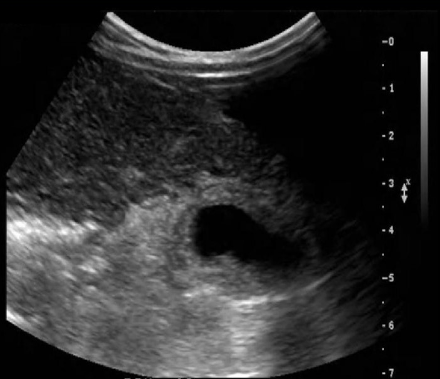

Identify this image.

Acute hepatitis